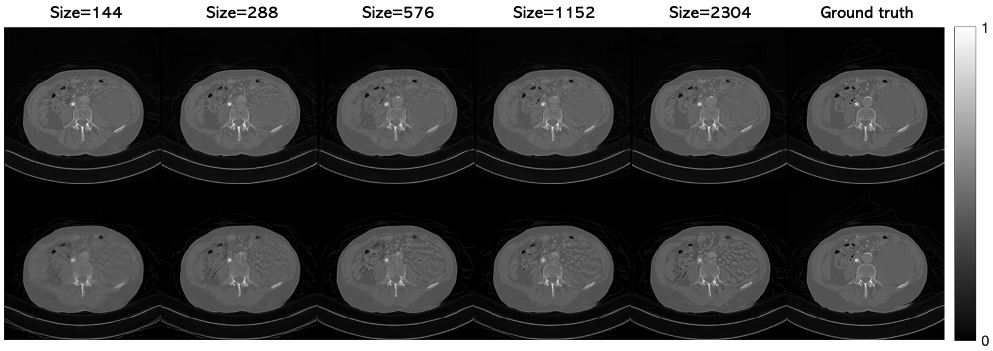

Effect of patch size.

We investigated the effect of the patch size PP used at reconstruction time for the 20-view CT reconstruction problem. We continued to augment the training with smaller patch sizes when possible so as to be consistent with the main experiments (patch size of 56 but also trained with patch sizes of 32 and 16), while using the same neural network architecture. Different amounts of zero padding were needed for each of the experiments per (3). App. A.4 provides the full details. At reconstruction time, the same patch size was used throughout the entire algorithm. Using a “patch size” of 256 corresponds to training a diffusion model on the whole image (without zero padding).

Table 5 shows that careful selection of the patch size is required to obtain the best results for a given training set size. If the patch size is too small, the network has trouble capturing global information across the image. Although the positional information helps in this regard, there may be some inconsistencies between patches, so the learned image prior is suboptimal although the patch priors may be learned well. At the other extreme, very large patch sizes and the whole image diffusion model require more memory to train and run. The image quality drops in this case as limited training data prevents the network from learning the patch prior well.

Figure A.5 shows the results of applying PaDIS to two example test images with different patch sizes. The main results, i.e., those shown in Table 1, used P=56P=56. For some of the other patch sizes, some artifacts can be seen in the images. Namely, the smooth parts of the image become riddled with "fake" features for small patch sizes and some of the sharp features become more blurred. The fake features in the right half of the image in the top row are especially apparent when applying the whole-image model. The runtime for different patch sizes were fairly similar, with P=8P=8 taking notably longer than the others due to the large number of patches required. The image size for these experiments was small enough so that the score function of all the patches could be computed in parallel; however, for larger scale problems such as high resolution 2D images or 3D images, large patch sizes become infeasible due to memory constraints.

Figure A.5: Results of PaDIS for 20 view CT reconstruction with different sized patches.